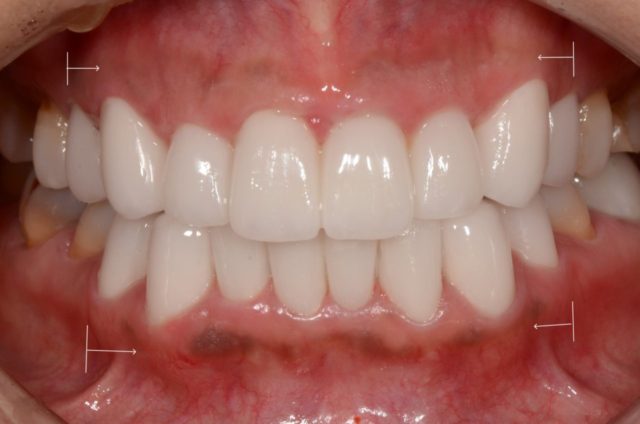

after

| 治療方法 | ジルコニアセラミッククラウンによる審美治療+ホワイトニングによる審美治療 (下の歯のホワイトニング後の色味よりもワンランク明るく作成) |

| 治療期間 | 3週間 |

| 費用 | 1,188,000円 |